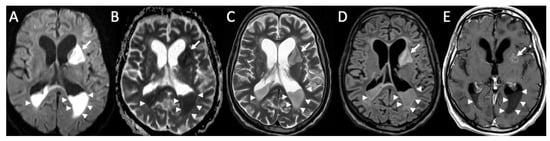

| Tuberculosis | • Leptomeningeal enhancement in the basal cisterns • Hydrocephalus very common • Infarcts in the basal ganglia due to vasculitis • Possible concomitant tuberculomas or miliary tuberculosis |

| Cryptococcus Neoformans | • Leptomeningeal enhancement • Cryptococcoma • Gelatinous pseudocysts |

| Candida albicans | • Microabscesses • Vascular lesions |

| Aspergillus fumigatus | • Abscesses • Vascular lesions |